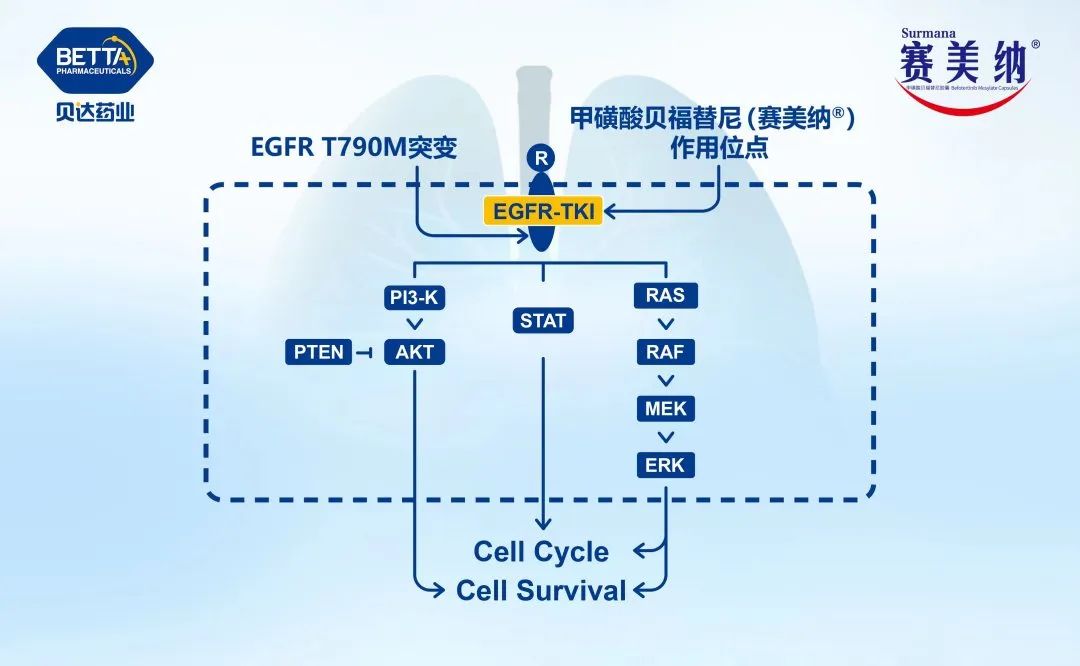

贝达药业甲磺酸贝福替尼胶囊非小细胞肺癌一线适应症获批上市...

贝达药业甲磺酸贝福替尼胶囊非小细胞肺癌一线适应症获批上市...